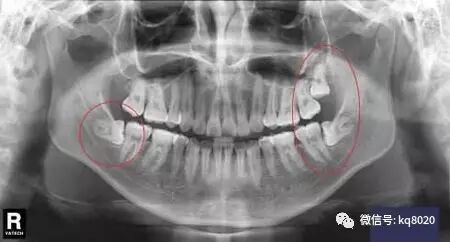

原因就是人类的进化,食物精细化,脸逐渐变窄,颌骨缩小,整个口腔呈慢慢变小的趋势。但是你要知道牙齿的数目和大小没有变化,而且智齿长出来比较晚,等它长出来的时候,其他28颗牙齿已经先入为主了,空间基本占满了,所以智齿没有足够的空间,只能以各种姿势出现在口腔中。横着、斜着、躺着、竖着、歪着、挤着,怎么舒服怎么来。

这图片是阻生智齿,也就包括横着长的智齿拔除,会比较复杂些,平常简单的拔牙就是用工具将牙齿拔掉,不用缝线,上个药就搞定啦。